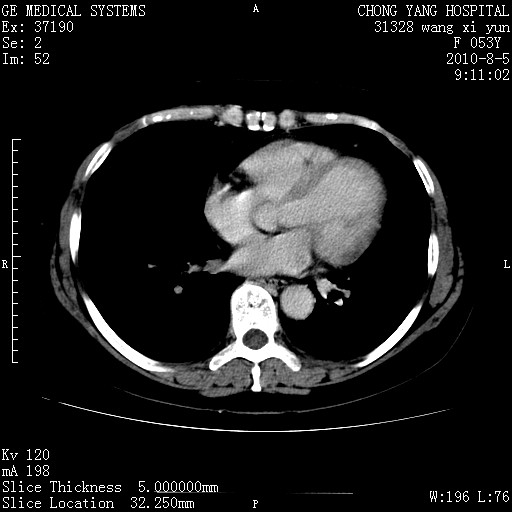

标题: CT28214:F41Y 血尿二十天,建议盆腔平扫加增强。

1)考虑肝左叶胆管细胞癌。2)脂肪肝。